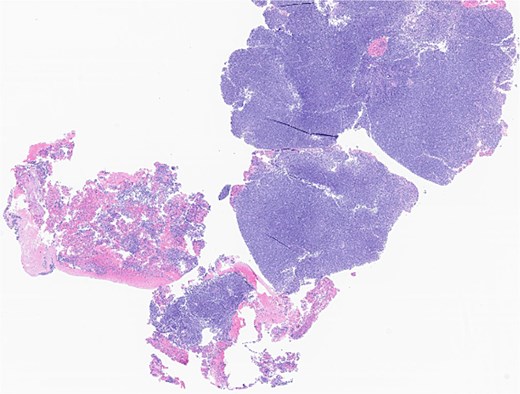

The patient underwent wide local excision of preauricular skin, parotidectomy, and selective left neck dissection (levels I–IV) (Fig. 2). Surgical pathology revealed poorly differentiated SCC involving subcutis, parotid, and surrounding soft tissues. In addition, CLL was found in three intra-parotid lymph nodes (Fig. 3). Immunohistochemistry showed cells positive for CD20, CD5, CD19, CD22, CD23, CD41, and BCL2, and negative for CD3, CD10, CD21, and cyclin D1. Flow cytometry revealed lambda light chain-restricted B-cells, with an absolute clonal B-cell count of 1.01 × 109/l, and 16.7% atypical lymphocytes in peripheral blood.

Left parotid tumor, biopsy: small lymphocytic lymphoma/CLL involving a lymph node.